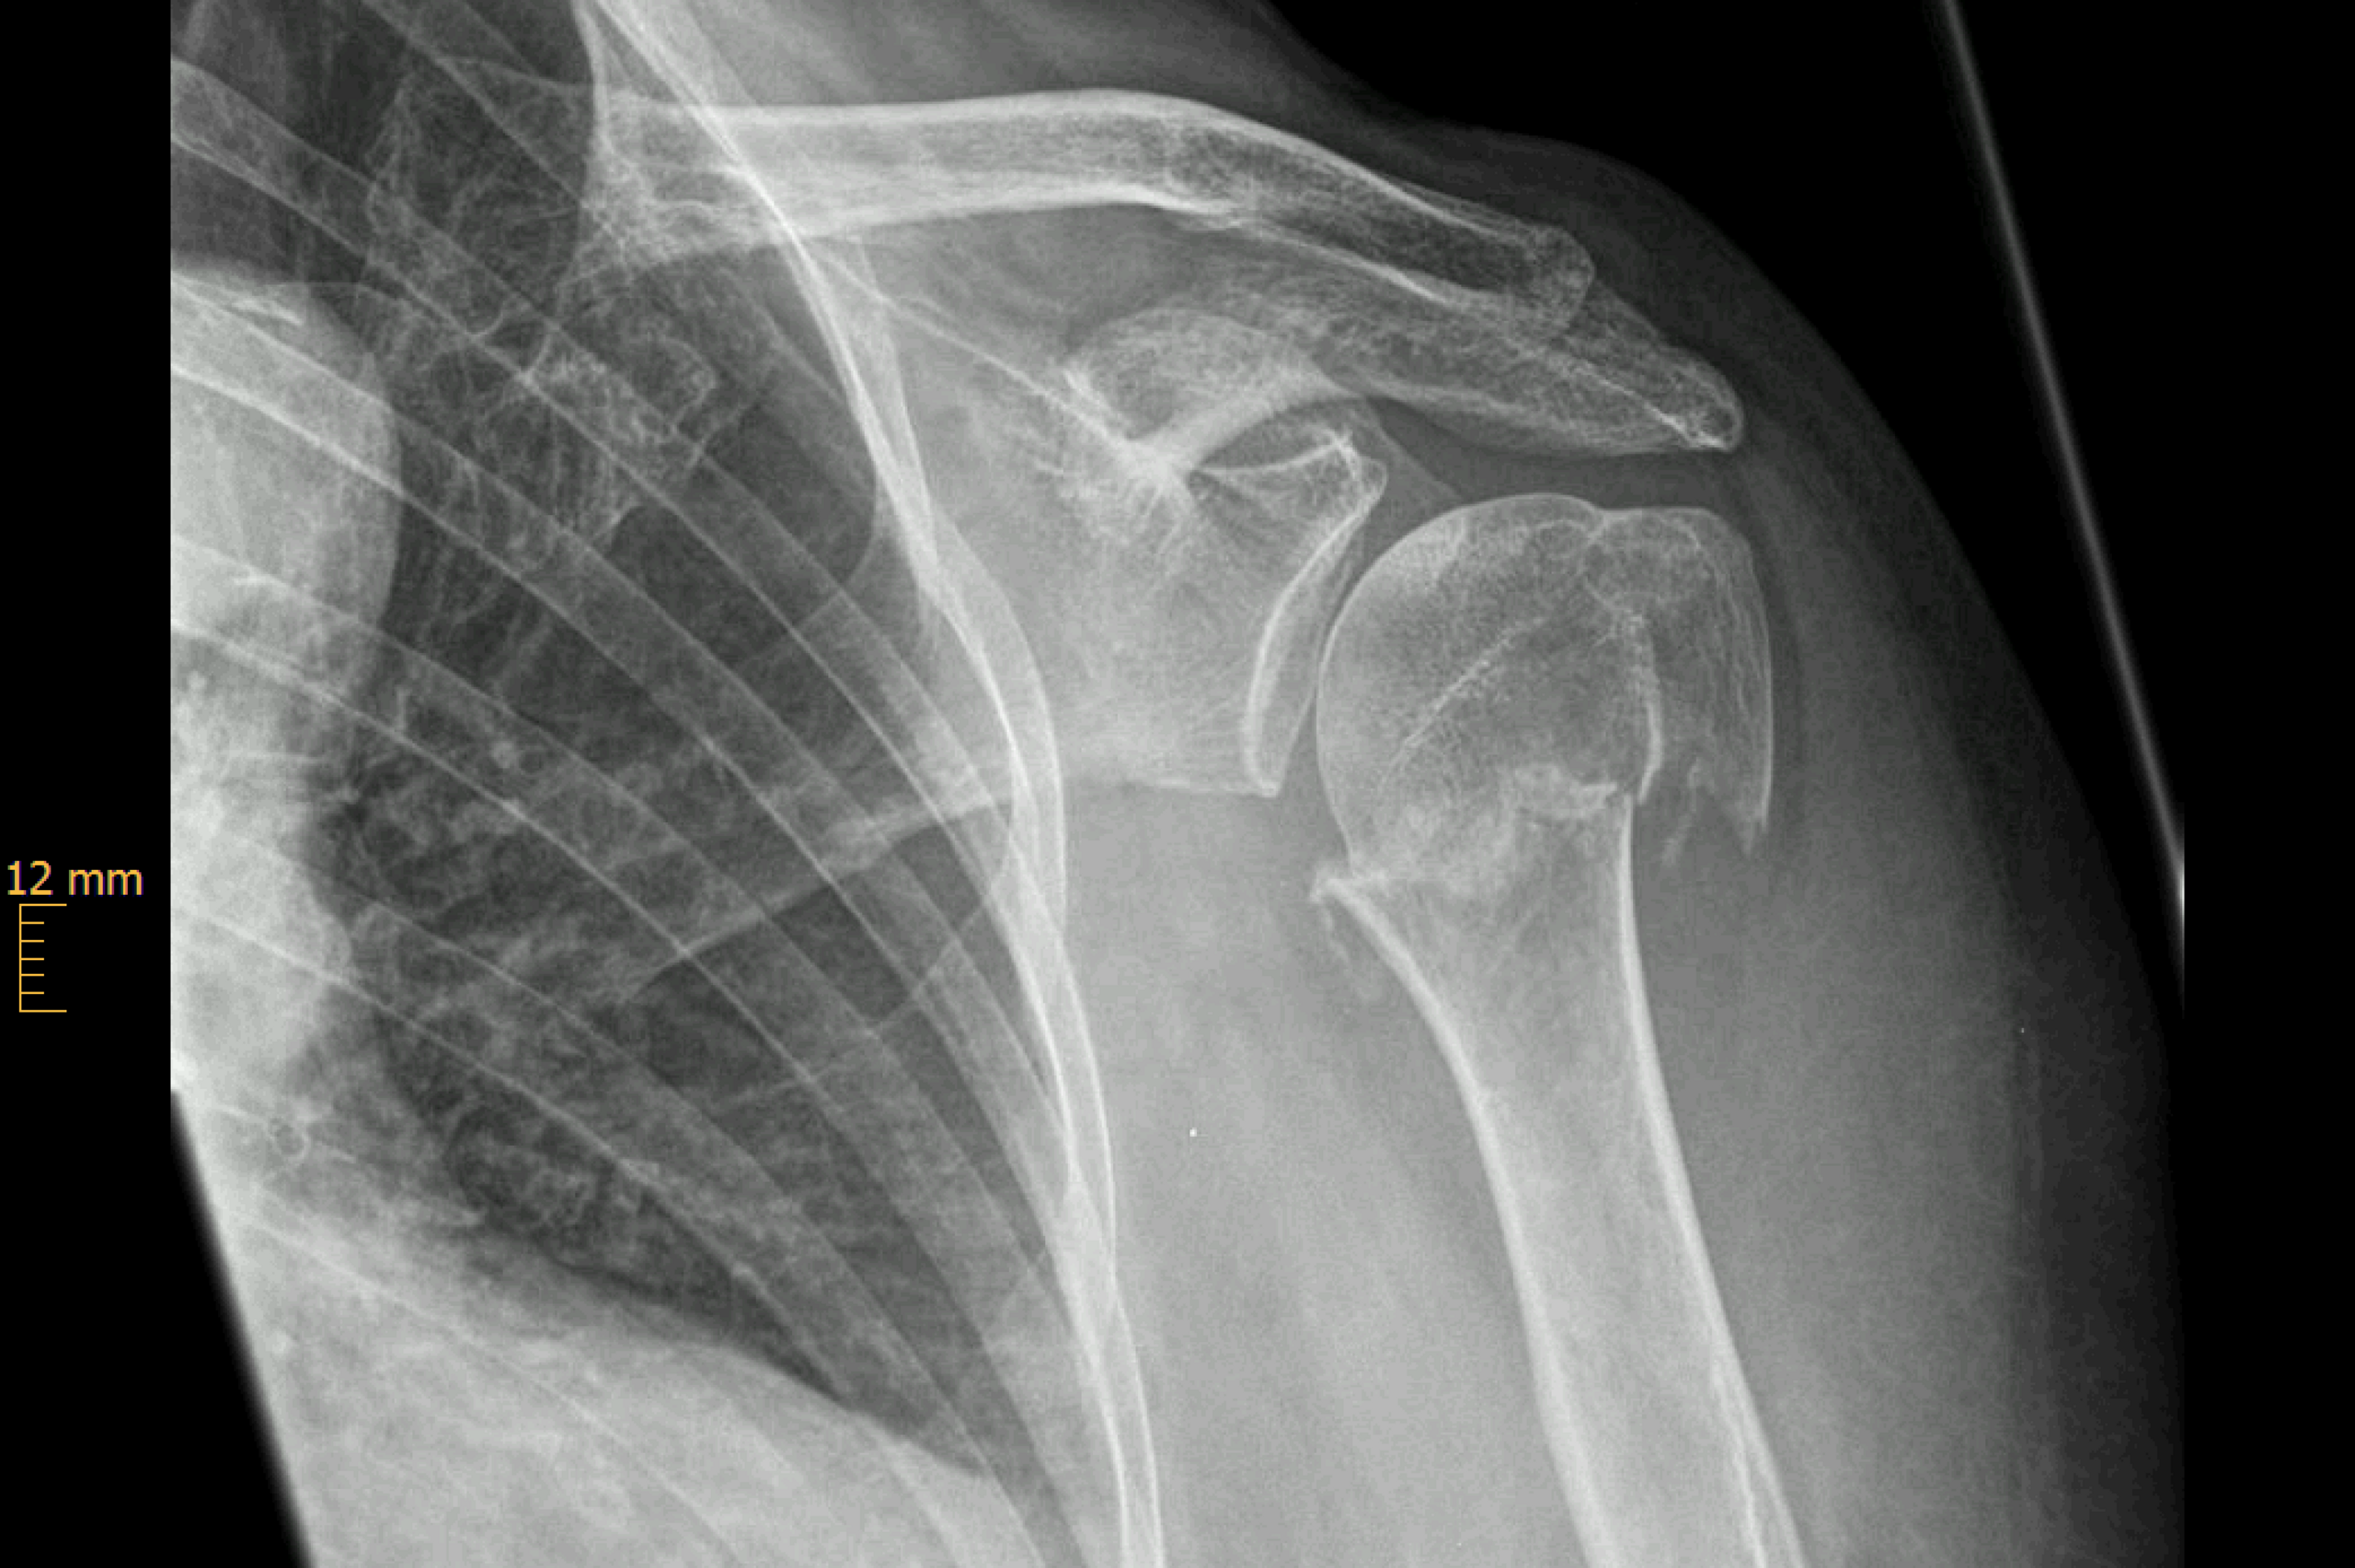

Klavikulafraktur (Schlüsselbeinbruch)

Die Klavikulafraktur ist eine typische Fraktur des jungen Patienten. Rad- und Motorradfahrer, Wintersportler und Kontaktsportler sind die typischen betroffenen Patienten.

Viele Schlüsselbeinbrüche können ohne Operation behandelt werden, wenn die Frakturstücken keine wesentliche Verschiebung (Dislokation) aufweisen. Der betroffene Arm wird in einer Armschlinge für ca. 3-4 Wochen ruhiggestellt, parallel wird mit physiotherapeutischen Behandlungen begonnen. Die Behandlungsdauer beträgt ca. 8 Wochen. Kommt es jedoch zu einer deutlichen Verschiebung der Frakturenden (um mehr als die Breite des Schlüsselbeins) und tritt dadurch eine Verkürzung oder ein Abknicken des Schlüsselbeins auf, besteht die Indikation zur Operation. Gleiches gilt auch für eine Fraktur des Schlüsselbeins mit vielen Bruchstücken (Fragmenten).